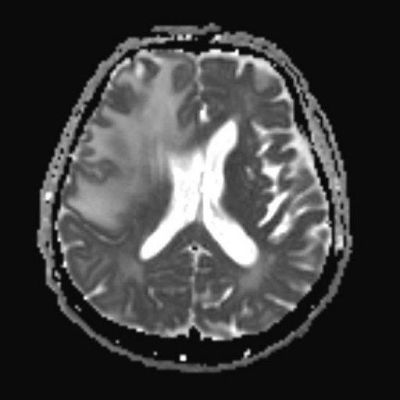

77 Y, E

1 aydır sol kol ve bacakta güçsüzlük, konfüzyon

Enfeksiyon markerları negatif